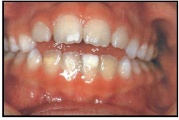

Laste ja noorukite söömishäired. Anorexia nervosa, Bulimia nervosa